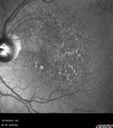

81 year old woman with vision loss in the right eye for a few weeks. She presented on oral antibiotic for preseptal cellulitis but had restricted eye movement from orbital cellulitis. Vision was LP right eye and 20/32 left eye. She went to the hospital and was admitted for IV antibiotics. She had no orbital abscess. Ultimately the right eye became NLP and she developed a necrotic retinal detachment and corneal neurotropic ulcer. The FA in this case shows brisk circulation. I presume she had a CRAO in the recent past and the central artery had reperfused. Left eye has Dry AMD.

Orbital Cellulitis - Optic nerve compression with ocular ischemia560 views81 year old woman with constricted eye movement, orbital cellulitis and severe vision loss in the right eye (LP). She has whitening of the retina and the OCT shows ischemic changes as well as subretinal fluid and blood. The vision in this eye declined to NLP and the eye remained ischemic despite control of her infection.     (0 votes)